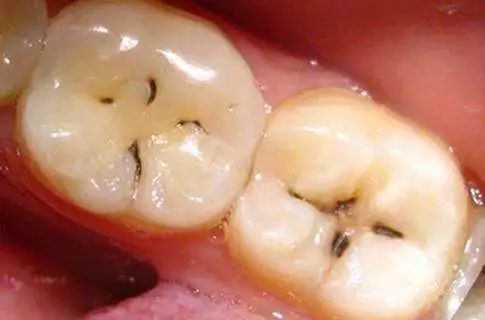

我们常说的后牙,学名第一磨牙和第二磨牙是磨碎食物的主要牙齿,也是最坚硬、最大的牙齿。首先我们需要了解后牙窝沟点隙的结构,即发育沟。后牙的表面即咬合面,一般会有四个隆起角,由牙胚发育而成。四个隆起部位之间形成沟壑点隙,这些沟壑的形态不同,而这些沟壑最容易附着堆积污垢细菌,形成窝沟龋,窝沟龋形态千变万化,每个人的样子都不同,但大致都会有明显的黑线模样。

窝沟的形态与龋坏的进展速度是密切相关的,窝沟是不易清洁的,在窝沟发生龋坏时,损害是从窝沟侧面开始(釉柱和密度决定),最后扩展到窝沟底部,当窝沟龋进一步发展,达到牙本质层时,龋坏速度就会加快。直到腐蚀到牙髓,疼痛就开始了。

一旦牙齿沟出现黑线,很不幸,说明你已经蛀牙了!不要单纯的以为那只是色素累积,早期蛀牙是没有龋洞的,平时饭后没有注意漱口,容易造成食物残渣堆积,给口腔细菌提供了营养,在唾液环境下,导致牙齿表面(牙釉质)被破坏。

有人觉得,过了这么久,黑线只是变粗了,又不会牙痛,如果你认为现在没有事,一直拖到一至两年,你想一下,口腔细菌腐蚀根本停不下来,很多人反映出现黑黑的牙洞时,牙本质被破坏,龋洞还会变大。早期的后牙有蛀牙是没有明显的龋洞,大多在咬合面有黑色的勾线,很多患者都以为那是色素沉着,洗牙时总是要求尽力把那洗去,殊不知那其实已经是龋坏。

其发展主要有三个阶段:①蛀牙基本形成,沟壑内附着细菌,牙齿表面黑线形成。②蛀牙侵蚀到牙本质内部,吃东西遇到冷热酸甜会感到不适,也由原来的黑线发展成较大的蛀洞。③蛀牙继续向下发展侵犯到牙髓,这时候出现明显的疼痛,龋洞更大,继续发展下去,整个牙齿就烂掉了。